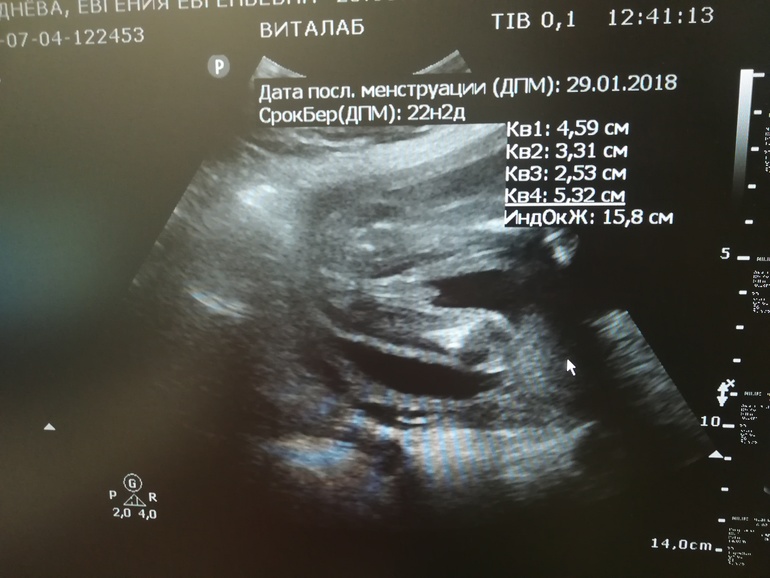

Пол малышаБыла сегодня на УЗИ. Хотела уже точно узнать пол, а также волновало, поднялась ли плацента (в 18н6дн была 1,1 см). Слава Богу, плацента сейчас стала 2,5 см, в 22н2дн.

Ну и подтвердили мальчика.. Рухнули мои мечты и надежды.. Ну ладно, Богу виднее кто мне нужен. Буду кошку в платья наряжать 😂